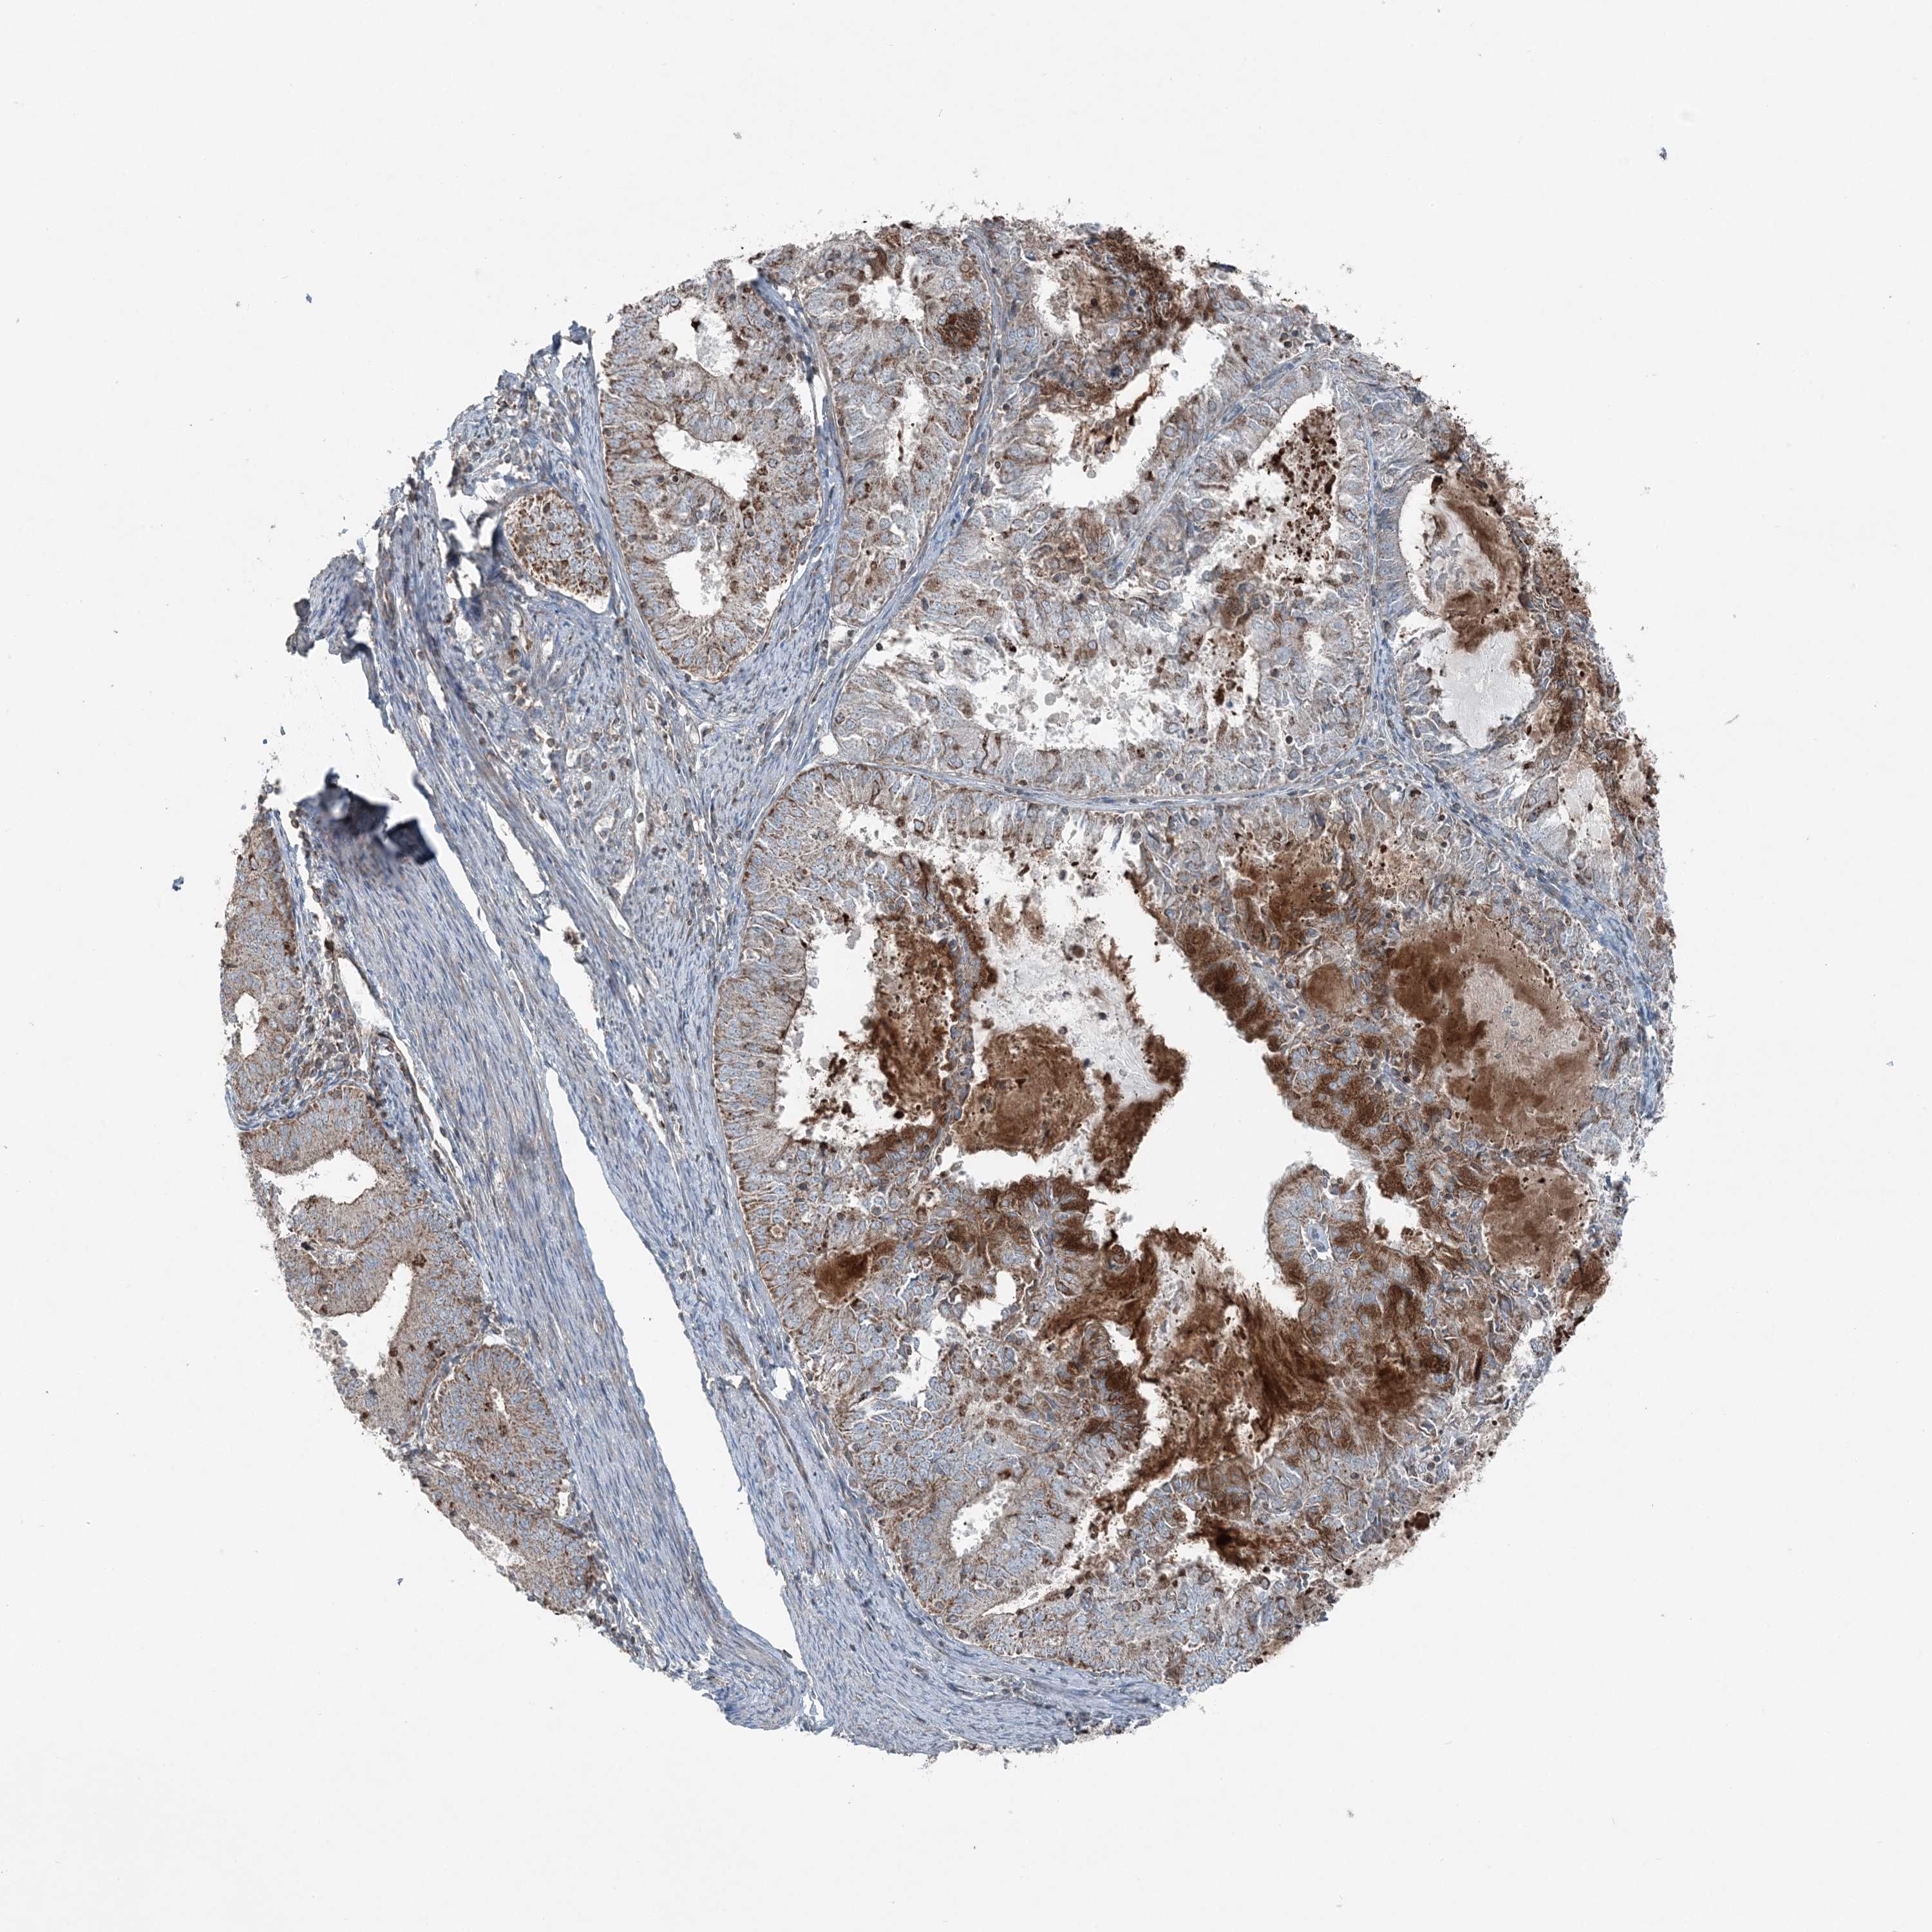

ENDOMETRIAL CANCER - Protein expressioni

A mouse-over function shows sample information and annotation data. Click on an image to view it in a full screen mode. Samples can be filtered based on level of antibody staining by selecting one or several of the following categories: high, medium, low and not detected. The assay and annotation is described here.

Note that samples used for immunohistochemistry by the Human Protein Atlas do not correspond to samples in the TCGA dataset.

Antibody stainingi

Antibody staining in the annotated cell types in the current human tissue is reported as not detected, low, medium, or high, based on conventional immunohistochemistry profiling in selected tissues. This score is based on the combination of the staining intensity and fraction of stained cells.

Each image is clickable and will lead to virtual microscopy that enables deeper exploration of all samples and also displays staining intensity scores, fraction scores and subcellular localization as well as patient and tissue information for each sample.

Antibody HPA036492

Antibody HPA036668

Staining

High

Medium

Low

Not detected

Intensity

Strong

Moderate

Weak

Negative

Quantity

>75%

75%-25%

<25%

None

Location

Nuclear

Cytoplasmic/membranous

Cytoplasmic/membranous,nuclear

Adenocarcinoma, NOS